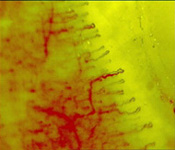

PICTURES (Continuously adjustable magnifying power)

Multi-location Multi - purpose. Microcirculation Microscope (ultra microscope,high-magnification microscope,high-resolution microscope)  is an advanced medical Instrument equipped with a special cold light source, all kinds of microscopic examination of the capillaries of the skin, mucosa and muscle are traumaless.It can be used for ecological observation, photographing and video-recording the microcirculatory status.

This instrument possesses a computerized microscopic (high-magnification microscope,ultra microscope,high-resolution microscope)  dim-light TV monitoring and an Microcirculation (ultra microscope) Image Data Analyzing System, being able to measure the diameter and the cross-section area of the microvessel, as well as the speed and the quantitative amount of blood flow. By means of image analysis, the density of microvessels could be evaluated and thrombotic masses can be isolated and clearly shown. This new instrument devotes to a newest scientific technique for observing the micro-world of medical studies. It has been effectively applied in many hospitals. Medical universities and scientific research, institutes in our country for ecological observations and the early diagnosis of microcirculatory changes in many clinical departments for various diseases, such as, shock, hypothermic anesthesia. reconstruction of amputated limbs, extracorporeal circulation, cardiac surgery ,burns. vasculitis, Raynauds diseases, hypertension, coronary disease, mycoardial inforction. cardiac failure, hepatitis, leukermia, anemia bronchial asthma, cerebrovascular diseases, pulmonary emphysema, corpulmonale, acute nephritis, chronic nephritis, peptic ulcer, pancreatits., diabetes mellitus, systemic lupus erythematosis. Rheumatoid arthritis, scleroderma, fulminant epidemic meningitis, toxic dysentery, pneumonia, toxemia of pregnancy, eclampsia. And so forth. It has also been practically used in the clinical wards of Dermatology, Chinese Traditional Medicine, Oncology, Acupuncture and Moxibustion. This instrument has been highly appreciated in being used in-cases of DIC( Disseminated Intravascular Coagulation) which is a life-threatening condition characterized by acute microcirculatory thrombosis followed by a severe critical acute microcirculatory failure.